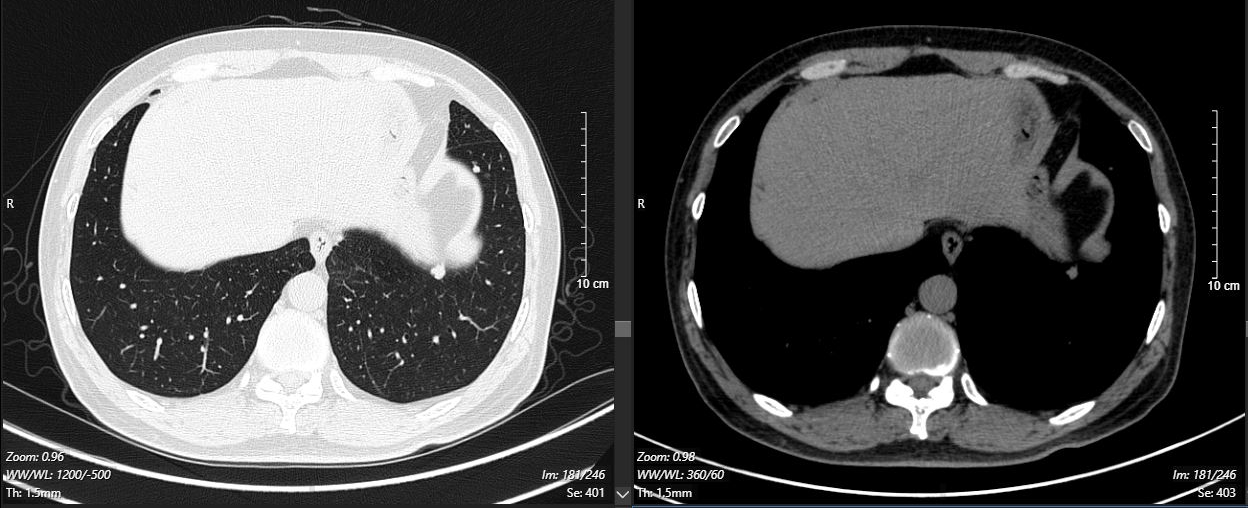

2024-11-26 胸部CT检查示:

2024-11-26 PET-CT进一步评估:左肺下叶背段近肺门处类圆形分叶状肿块(约32*28mm),FDG代谢异常增高;纵隔内4L组、左下肺门处、左侧膈肌脚内侧见稍大淋巴结FDG代谢增高,左肺内及胸膜下散在多发结节影,FDG代谢不同程度增高,考虑左肺下叶肺癌伴左肺及胸膜多发转移、多发淋巴结转移。

治疗5个月后(2025-05-07):复查CT显示左肺病灶显著缩小,达到PR,肺内结节明显吸收。